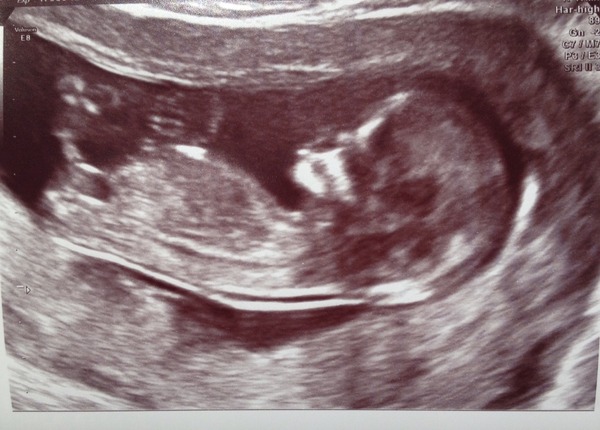

So there's a super chilled out, thumb-sucking little bundle of adorable in my belly. GrinGrinGrin SO PLEASED. I'm finally starting to feel like I can relax and enjoy this pregnancy. Smile

Based on the size of the little'un they wanted to bring my EDD forward by 3 days, but I declined. I know I couldn't have conceived that early & I'd rather not be unnecessarily hassled for induction, so I'm sticking with Jan 13th.

I don't think we're going to find out baby's gender before s/he's born, but I do love a good guess. So here's my scan picture. Nub theorists, do your best! Smile